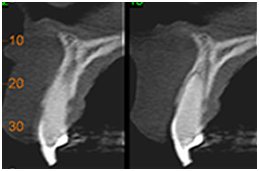

• Determinar quantidade, qualidade e inclinação do rebordo ósseo alveolar

Implantodontia Implantodontia